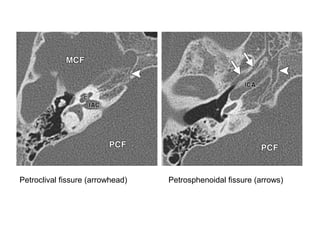

Petroclival fissure (arrowhead) Petrosphenoidal fissure (arrows)

Petroclival fissure (arrowhead)Petrosphenoidal fissure (arrows)